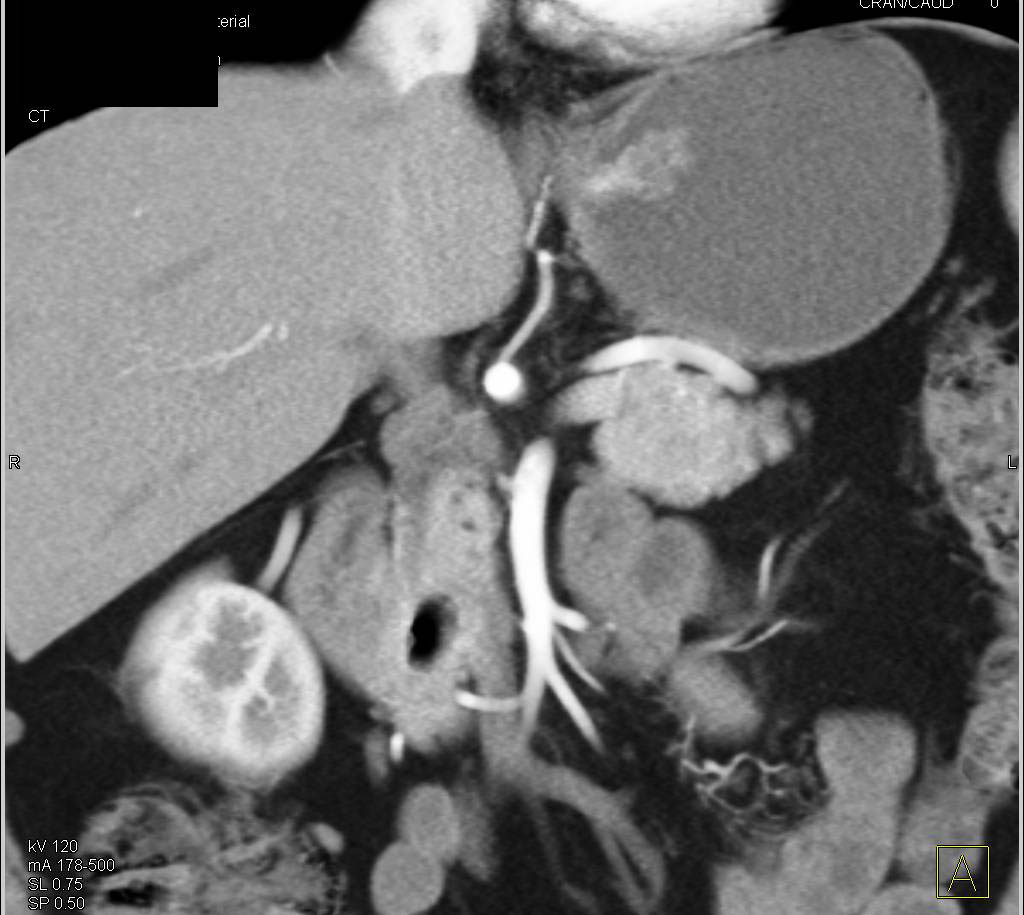

Gastric Diverticulum Simulates an Adrenal Mass